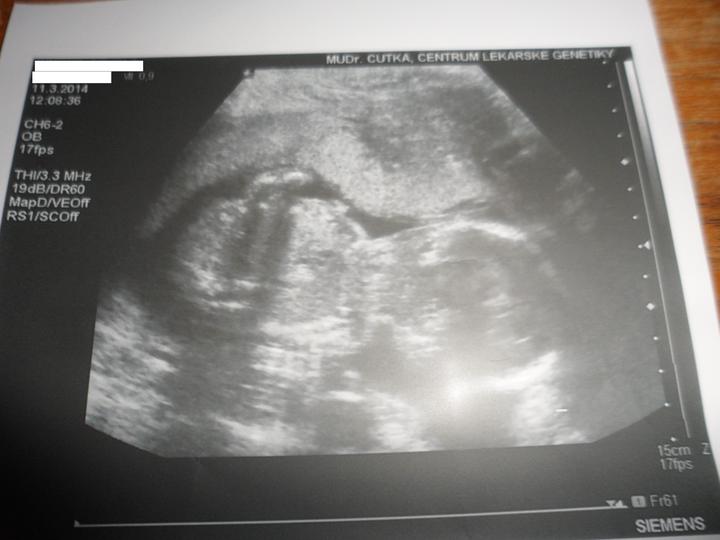

Holky nemáte zkušenosti s Centrum lékařské genetiky v Českých Budějovicích? Jsou tam v pohodě?